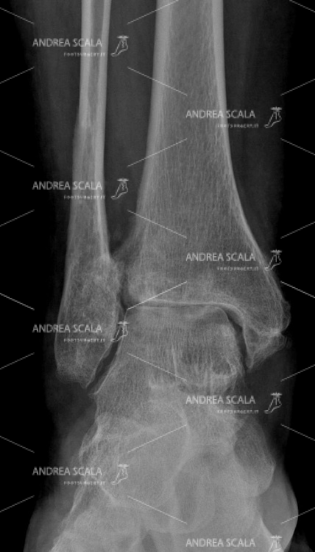

Si pensi che, addirittura, anche il solo atto di rimanere in piedi a lungo è una fonte di stress per l’arto che, col passare del tempo, diventa sempre più vulnerabile e quindi più facilmente soggetto a traumi. Per questo, quando un soggetto manifesta dolore oppure soffre di processi di artrosi degenerativi, il medico chirurgo ed ortopedico del piede può arrivare a consigliare un’operazione di protesi di caviglia.

Un intervento che permette di evitare che il dolore e la rigidità causati dal consumo incessante delle cartilagini peggiorino vorticosamente, arrivando a rendere difficile la normale deambulazione con serie conseguenze limitative sui movimenti ed invalidità. L’operazione, infatti, permette ai pazienti di riprendere le loro attività sin da subito, ovviamente con le dovute accortezze ed un piano di riabilitazione seguito passo passo con il proprio specialista.

In particolare, per un corretto montaggio della protesi, occorre rispettare l’anatomia della caviglia, facendo attenzione a conservare le parti anatomiche più delicate, come l’astragalo e i legamenti, nel modo migliore per evitare l’instabilità. In secondo luogo, poi, va rispettata anche la biomeccanica della caviglia, mantenendone l’allineamento. La protesi, infatti, viene stabilizzata ad ogni passo e non subisce carichi asimmetrici.